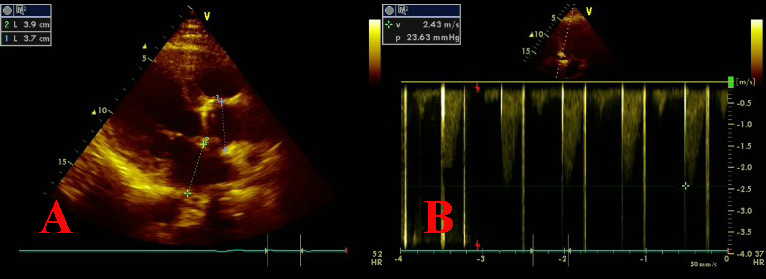

We present a case of an acute myocardial infarction with ST segment elevation in a patient with a mechanical aortic valve prosthesis who had discontinued anticoagulant therapy. We performed a primary coronary intervention procedure, including thrombus aspiration as well as plain balloon angioplasty (low atmospheres), in order to restore coronary flow in left anterior descending artery as soon as possible. Review of the literature suggests that in such cases the diagnosis of the embolic origin of the acute coronary syndrome is assumed and can never been proved definitely. Thrombus aspiration must be included in the therapeutic strategy of these patients.